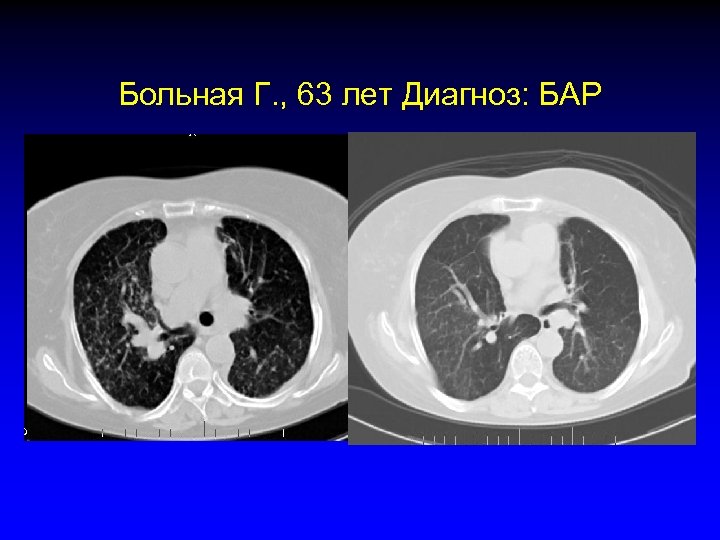

Больная Г. , 63 лет Диагноз: БАР • 2003 год. Резекция нижней доли левого легкого по поводу узловой формы БАР • 2004 год. Рецидив заболевания диффузная форма БАР, ПХТ 1 -я линия (платина) • 2005 январь. Прогрессия заболевания, 2 -я линия ХТ (таксол) • 2005 май. Прогрессия заболевания, 3 -я линия терапии (иресса) • 2005 июль. Частичный ответ • 2005 сентябрь. Полный ответ

Больная Г. , 63 лет Диагноз: БАР